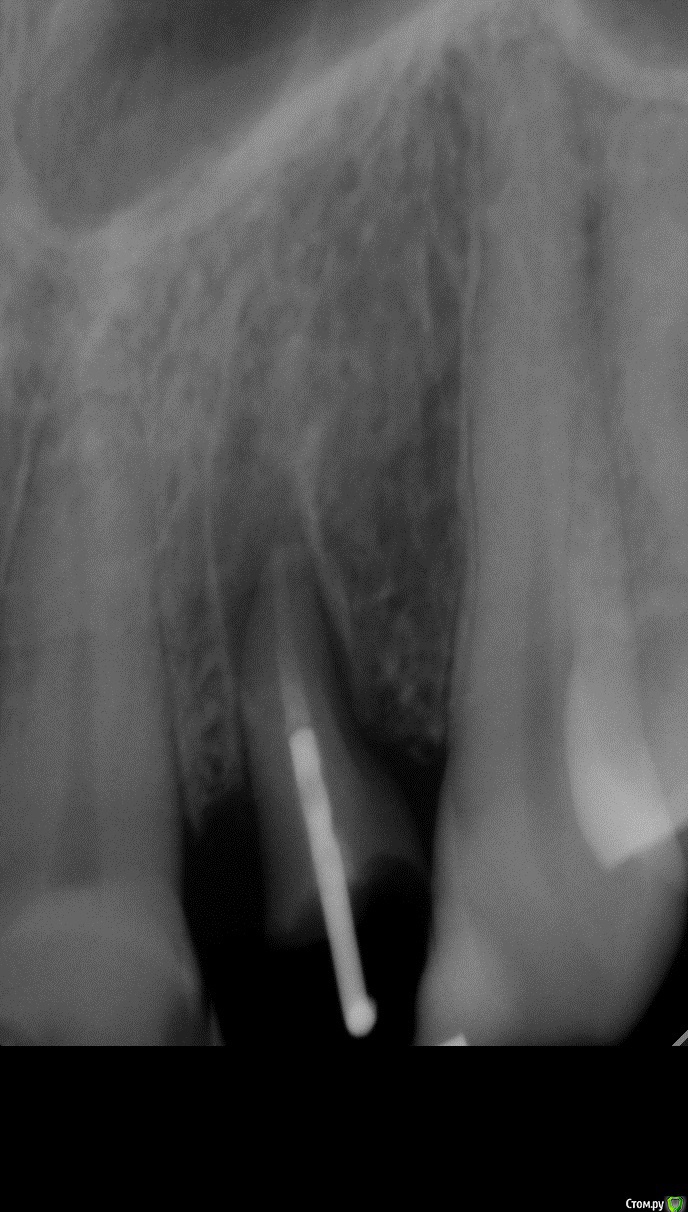

zzkz Опубликовано 10 июня, 2015 Поделиться Опубликовано 10 июня, 2015 здесь хирургическая екструзия как удаляли, периотомом связку то рвем? Ссылка на комментарий

Sundance Опубликовано 10 июня, 2015 Автор Поделиться Опубликовано 10 июня, 2015 как удаляли, периотомом связку то рвем?да но на корне остаются места со связкой и чем их больше тем больше шансов что будет полное востановление приодонта , правда в етом случаи другая ситуация корень уходил под кость на 2 мм пришлось на недельку поставить ортодонтическую тягу и только после етого удалять Ссылка на комментарий

Sundance Опубликовано 10 июня, 2015 Автор Поделиться Опубликовано 10 июня, 2015 И сколько по времени? при хирургической екструзии через 3 недели после удаления можно нагружать Ссылка на комментарий

Romanson Опубликовано 10 июня, 2015 Поделиться Опубликовано 10 июня, 2015 Как такие зубы шинируются, и через какое время шина снимается? Ссылка на комментарий